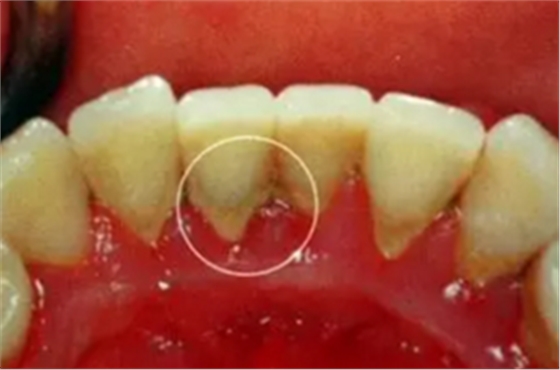

牙結(jié)石是指沉積在牙面上的礦化的菌斑,根據(jù)其沉積部位和性質(zhì)分為齦上牙結(jié)石和齦下牙結(jié)石兩種。

(1)齦上牙結(jié)石

位于齦緣以上的牙面上,肉眼可直接看到。在牙頸部沉積較多,特別是在大涎腺導(dǎo)管開口相對處,如上頜磨牙的頰側(cè)和下頜前牙的舌側(cè)沉積更多。齦上牙石中無機(jī)鹽的主要來源是唾液中的鈣、磷等礦物鹽。